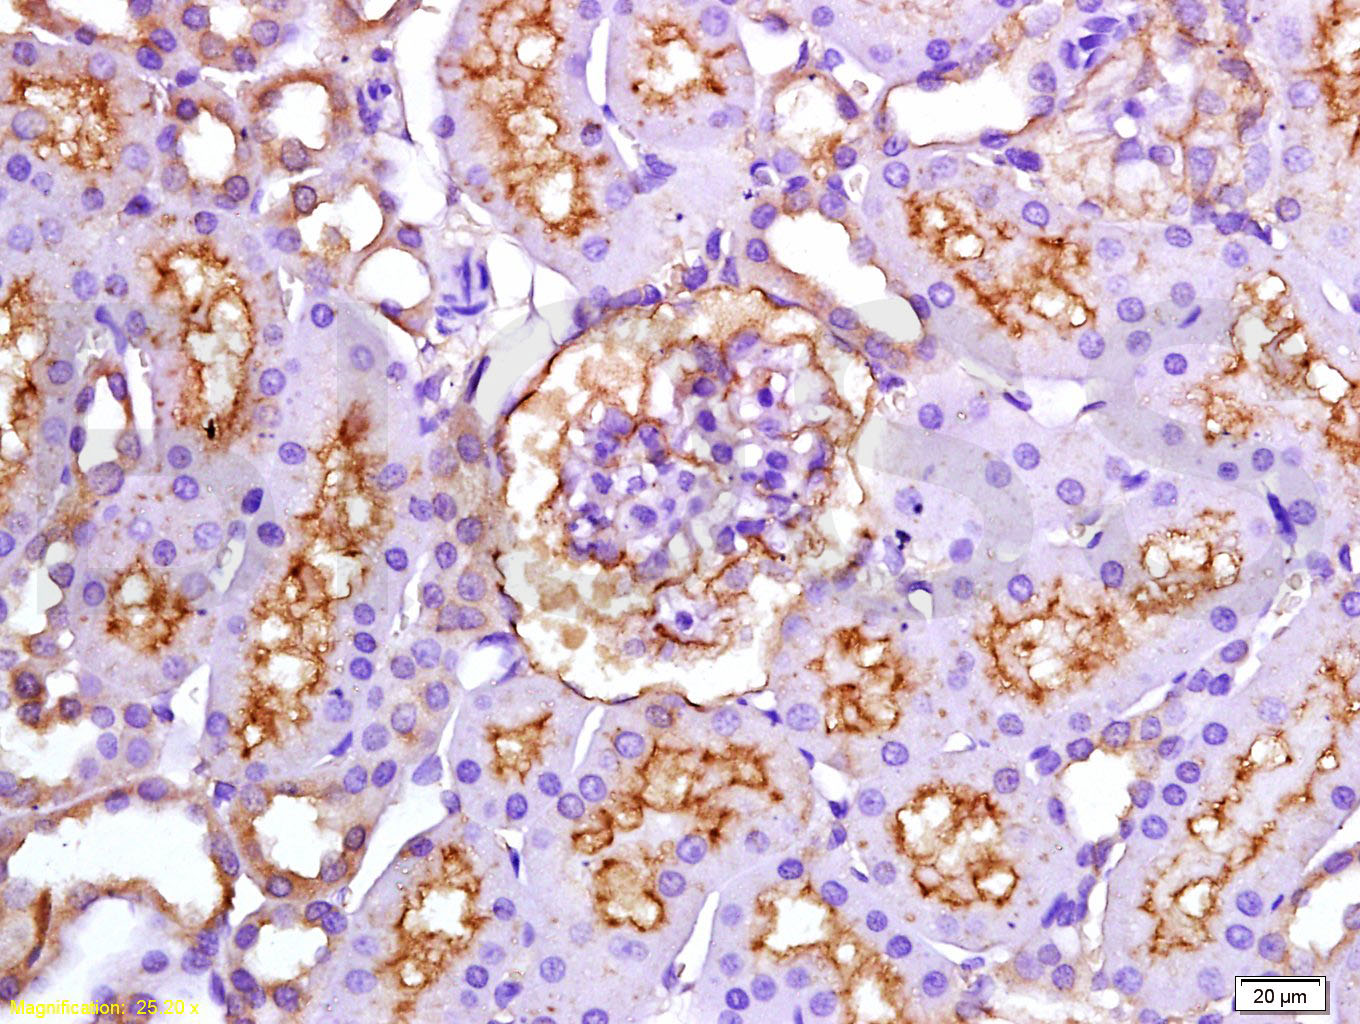

Tissue/cell: rat kidney tissue; 4% Paraformaldehyde-fixed and paraffin-embedded; Antigen retrieval: citrate buffer ( 0.01M, pH 6.0 ), Boiling bathing for 15min; Block endogenous peroxidase by 3% Hydrogen peroxide for 30min; Blocking buffer (normal goat serum,C-0005) at 37℃ for 20 min; Incubation: Anti-ET-1 Polyclonal Antibody, Unconjugated(bsm-0954M) 1:200, overnight at 4°C, followed by conjugation to the secondary antibody(SP-0024) and DAB(C-0010) staining